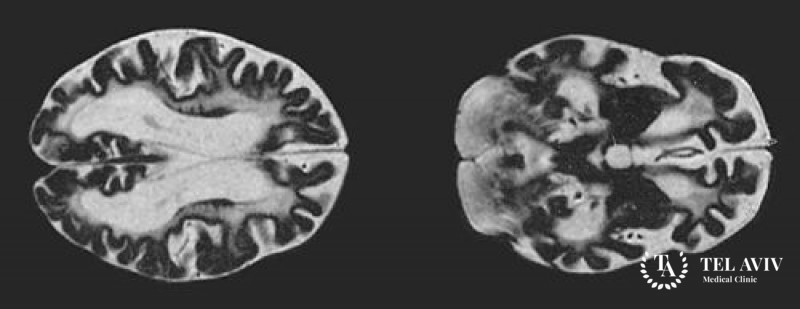

- МРТ;